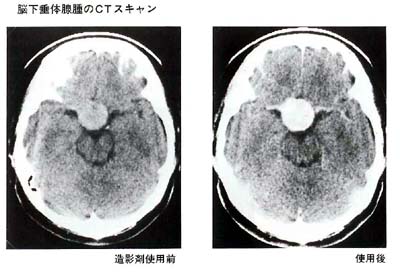

(2)CTスキャン

(1)は脳下垂体を包んでいる骨の変化を調べるもので、いわば腺腫の間接的な診断にすぎません。

一方、CTスキャンは腺腫自体を描出できますので、その正確な大きさと拡がりを知ることが可能です。造影剤を点滴する前と後とで2回検査を行い、その差を調べます。この際、まれに造影剤によってじんましん等アレルギー症状を示す方がいます。